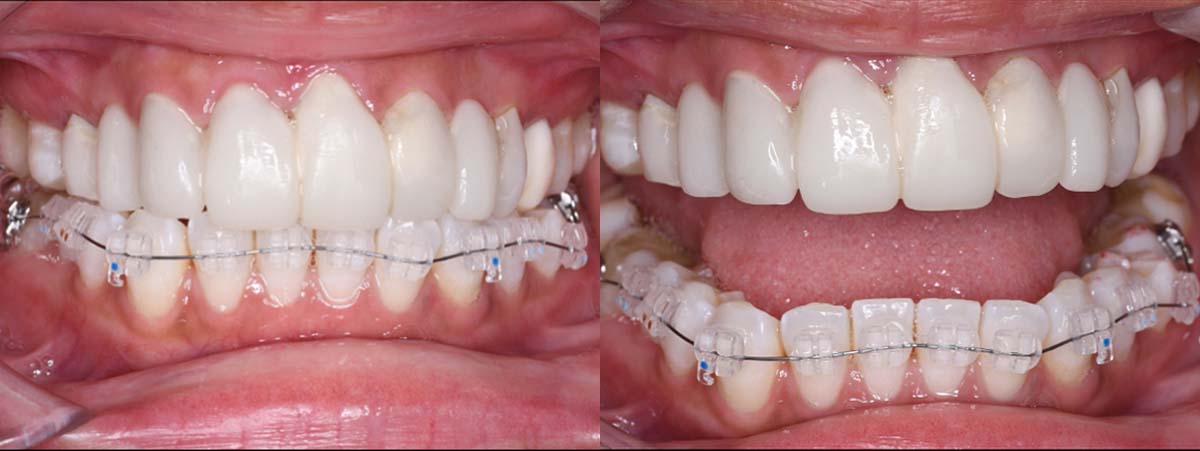

2024年 10月 下顎MTM開始

2024年 10月10日

10月21日

11月7日

11月28日